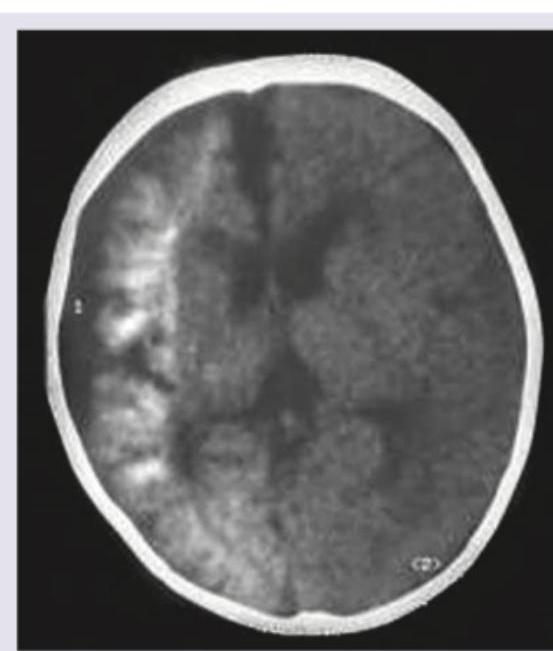

CT scan of a child with intellectual disability, recurrent seizures and hemangioma. Diagnosis is:

Explanation: ***Encephalofacial angiomatosis*** - This syndrome, also known as **Sturge-Weber syndrome**, is characterized by a classic triad of **facial cutaneous angioma (port-wine stain)**, **leptomeningeal angioma**, and **ocular involvement** (e.g., glaucoma). - Neurological manifestations typically include **seizures** and **intellectual disability**, while imaging like CT scans often reveal **gyriform calcifications** in the affected cerebral hemisphere (often described as "railroad track" calcifications). *Epilolia* - This term is a general and somewhat archaic description for a **convulsive disorder**, not a specific syndrome characterized by the presented clinical and imaging findings. - It lacks the specificity to explain the combination of **hemangioma**, intellectual disability, seizures, and the classic CT findings. *Louis-Bar syndrome* - Also known as **ataxia-telangiectasia**, this is a rare, neurodegenerative, inherited disease characterized by progressive **cerebellar ataxia**, **oculocutaneous telangiectasias**, and **immunodeficiency**. - The clinical presentation (especially the type of hemangioma and seizures) and typical imaging findings (cerebellar atrophy) are distinct from those described in the question. *Neuronal ceroid lipofuscinoses* - This is a group of **neurodegenerative lysosomal storage disorders** characterized by the intracellular accumulation of **lipopigment** in neurons and other cells. - The primary symptoms include **progressive intellectual and motor deterioration**, **seizures**, and **visual loss**, but they do not typically present with **hemangiomas** or the characteristic gyriform calcifications seen on CT.